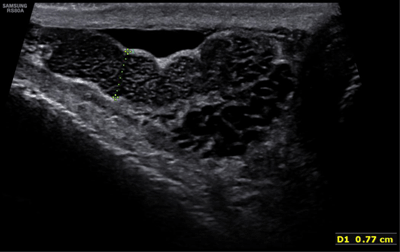

Figure 1

Enlargement of the right epididymis with multiple small cystic dilatations.